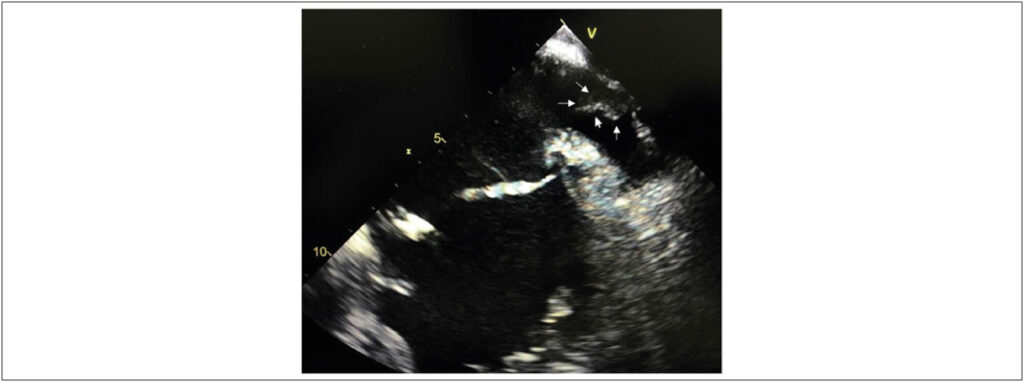

O Eco TEE é considerado exame padrão-ouro paradetecção de trombos em AAE., Com aincorporação da angio-TC de coração na prática clínica, tornou-se mais frequente o diagnósticode “falsa” imagem de trombo, o chamado pseudotrombo, em AAE, explicadopela falha de enchimento do contraste, devido à velocidade de fluxo reduzida nas trabéculas do AAE. Recentemente, coma utilização de protocolos específicos para avaliação de trombos na angio-TC e captação de imagens tardias, houve melhora significativa de sua sensibilidade e sua especificidade, com estas chegando próximas a 100% em algumas séries, e tornando-se, assim, opção menos invasiva ao ETE. Ela tem sido muito utilizada no pré-operatório de ablação por cateter para tratamento da FA ou oclusão percutânea do AAE.

Destaca-se, neste caso, o diagnóstico do pseudotrombo no ETE, que correspondia a artefato de estrutura extracardíaca metálica (stent) intimamente relacionado ao AAE, somente identificado na angio-TC cardíaca e que foi relevante no tratamento do paciente.